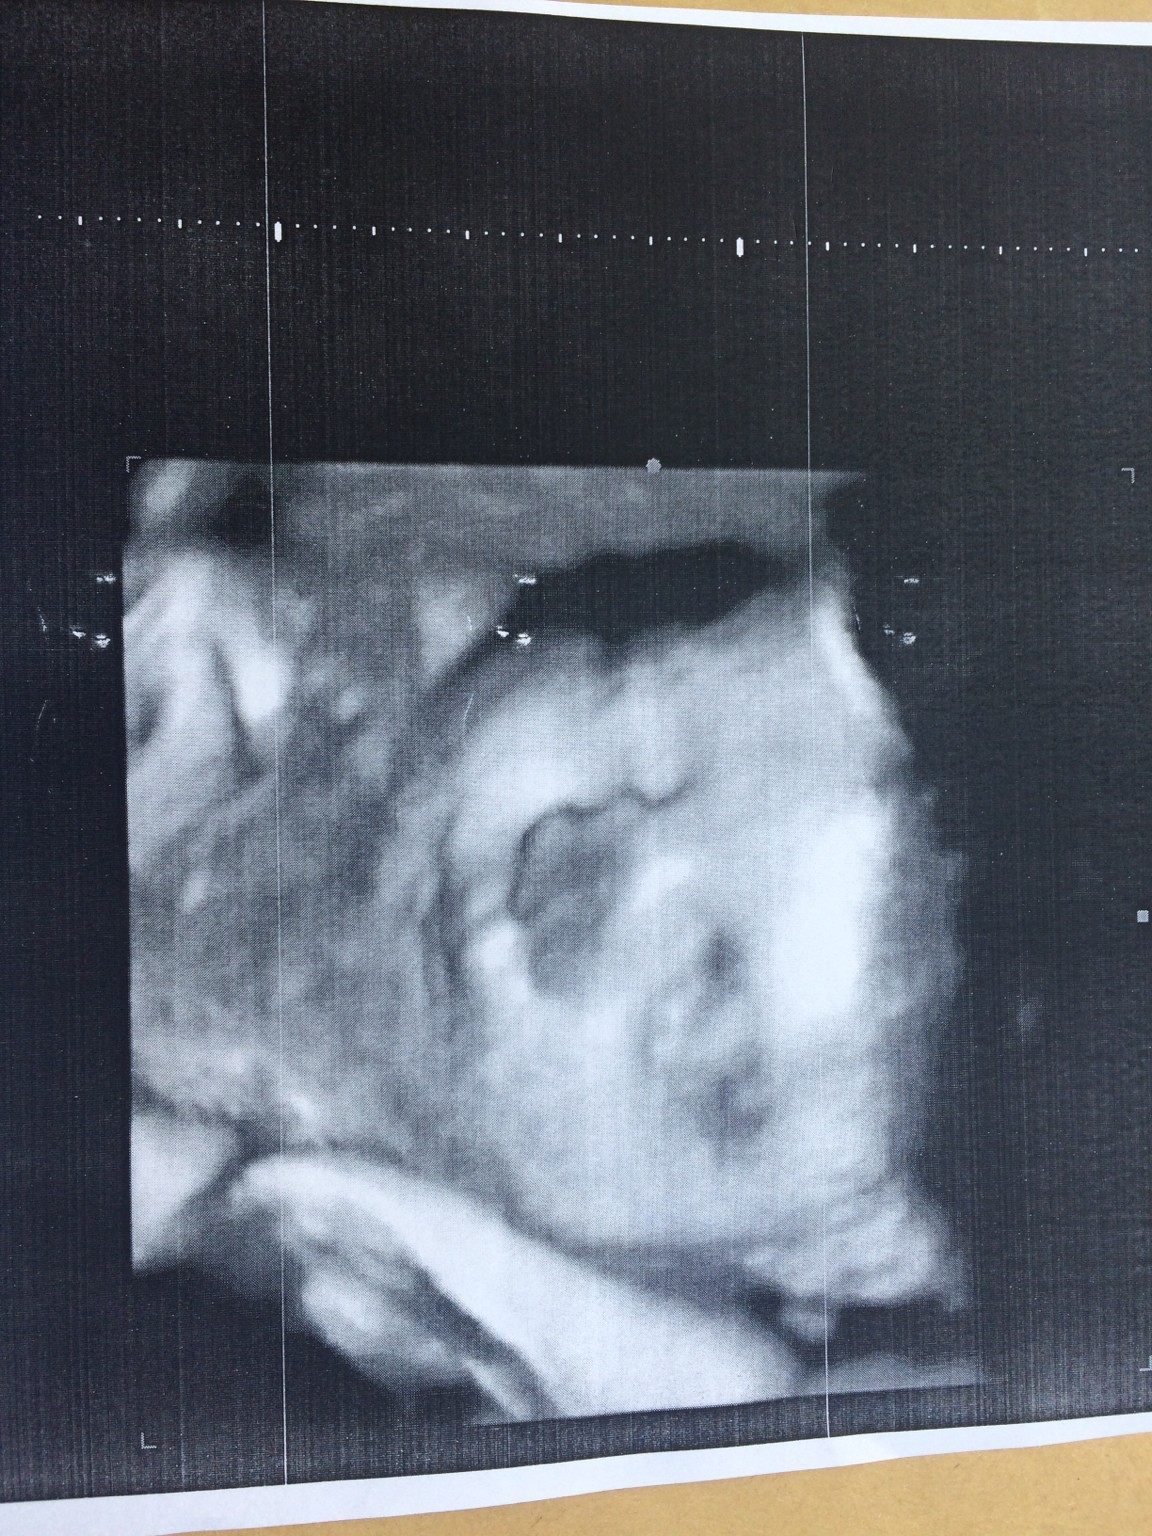

Mały waży 1700g. To 30+3 tc. Nie chciał pozować. Wtulił się w mamusie i nie chciał ładnie odwrócić buźki. Na jednym zdjęciu troszkę widać usta nosek i taki pućkowaty policzek. Ja jestem 9 kg na plusie. Przekroczyłam 70tkę.. jeszcze dwie wizyty przede mną. Kolejna 9.07. Wtedy pobierze wymaz na Gbs i określi przybliżoną wagę dziecka. W ciągu dwóch ostatnich miesięcy dziecko może podwoić swoją wagę. To wychodzi że mały może mieć z 3500g. Jak w pierwszej ciąży miałam gbs + to nie jest powiedziane , że teraz też tak będzie.